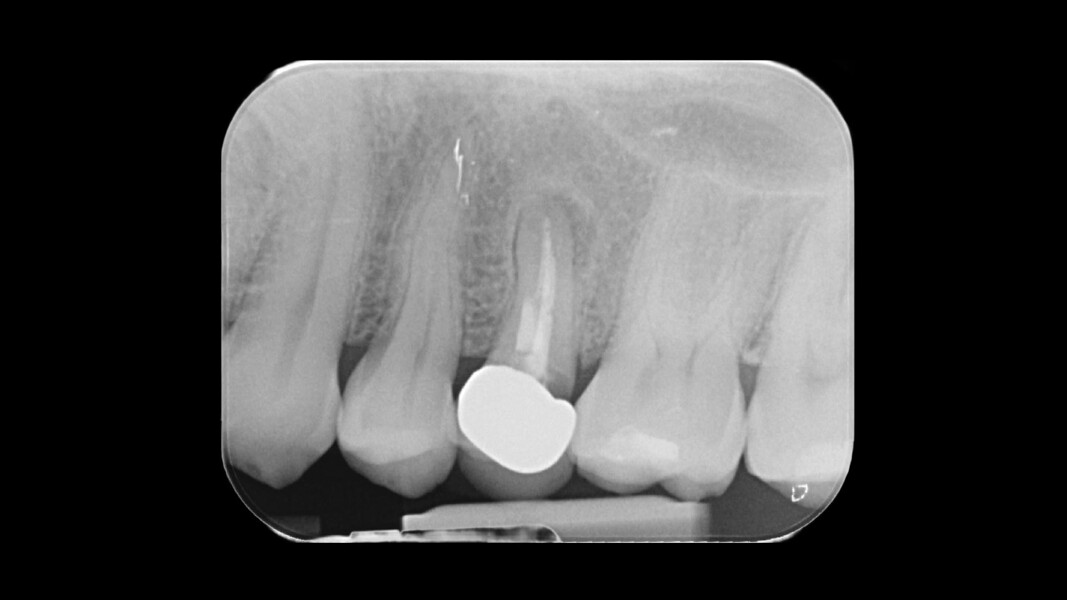

Una paziente di 50 anni presentava un premolare superiore non recuperabile. Dopo CBCT preoperatoria (T0) (Fig. 1), si è proceduto all’estrazione atraumatica e alla gestione dell’alveolo mediante posizionamento vestibolare di una membrana corticale eterologa (Lamina fine 0,7 mm, 35 × 15 mm, OsteoBiol) e riempimento con spugne di collagene (Figg. 2, 3). Sono stati applicati punti di sutura in nylon non riassorbibile 4/0. Dopo sei mesi di guarigione, una nuova CBCT (T1) ha consentito la valutazione della qualità ossea. Per la fase implantare è stato eseguito un lembo secondo la tecnica del roll flap, con preservazione delle papille interdentali e aumento del tessuto cheratinizzato (Fig. 4). È stato inserito un impianto JD Evolution Plus (4,3 × 11,5 mm) ottenendo un’eccellente stabilità primaria. Durante la chirurgia è stato prelevato un campione osseo per analisi istologica (Fig. 5).  Il lembo è stato suturato con nylon 4/0 intorno all’abutment di guarigione. Dopo due mesi, la paziente è stata riabilitata con una corona monolitica in zirconia realizzata da impronta digitale intraorale (Fig. 6).

L’analisi CBCT ha evidenziato un mantenimento del volume osseo con valori comparabili tra T0 e T1.

• T0: larghezza 9,22 mm, altezza 17,12 mm;

• T1: larghezza 9,46 mm, altezza 17,02 mm.